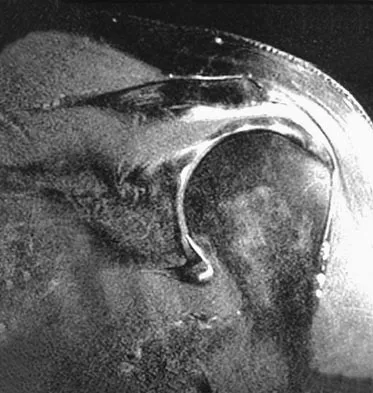

A 37-year-old man has left shoulder pain and weakness. Coronal T1- and axial T2-weighted MRI scans are shown in Figures 17a and 17b. The biopsy specimen is shown in Figure 17c. What is the most likely diagnosis?

Explanation